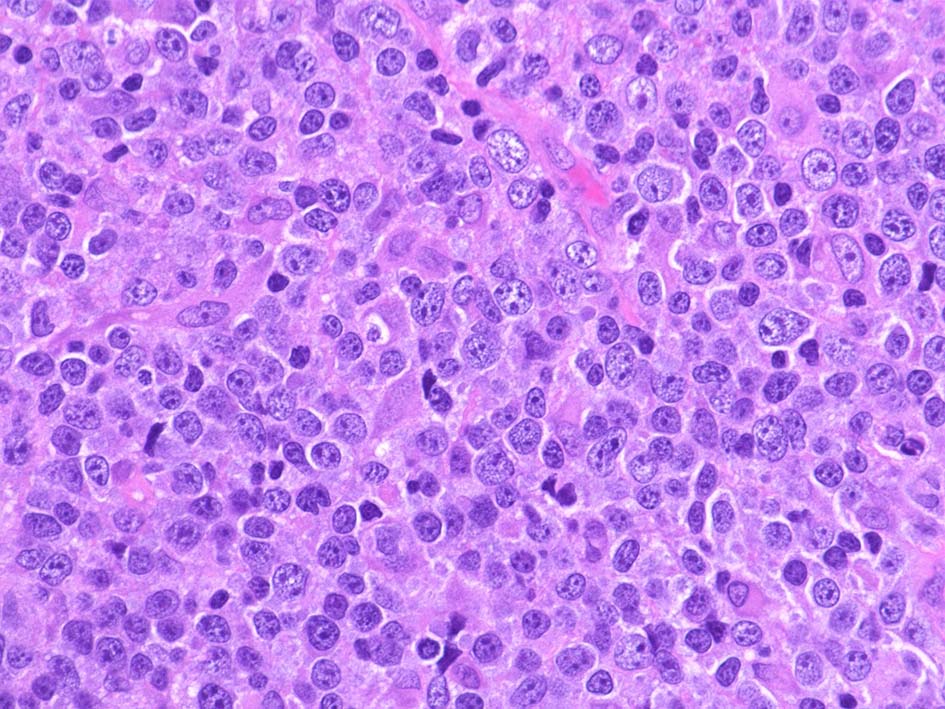

DLBCL, Not Otherwise Specified

Centroblastic (胚中心芽球型)

Centroblastic variant(胚中心芽球型)

• 最も多くみられるtype.腫瘍細胞は胚中心, centroblastに似る. (核膜に付着するように核小体が2~4個認められる)

• 核はほぼ均一な大きさのことが多いが, ときに大小不同がめだつこともある.まれに分葉ないし多核に見える細胞が混在.

免疫芽球が混在することもある.

• 分葉構造がめだつことがあり, 節外性に多い. GCBが多い.

血液病理学者が腫瘍細胞形態に基づいてDLBCLをサブタイプ化しようと試みたが,観察者および観察者群間の再現性が乏しく, 結果として, WHOリンパ性腫瘍組織分類においてDLBCLとして単一の診断カテゴリーにまとめられている.*29